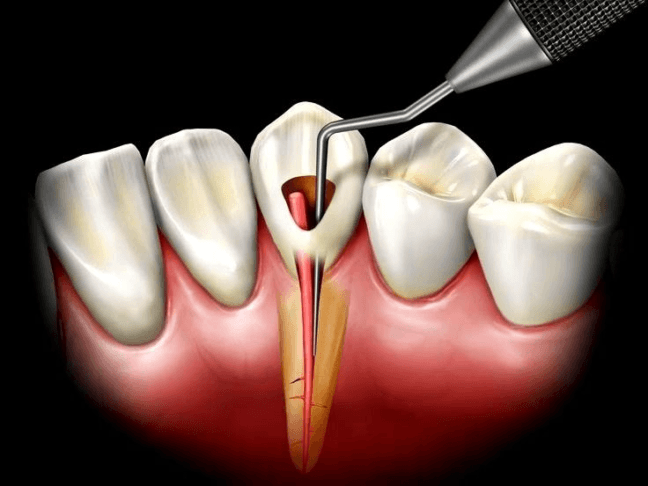

- Dentistry

Treatments